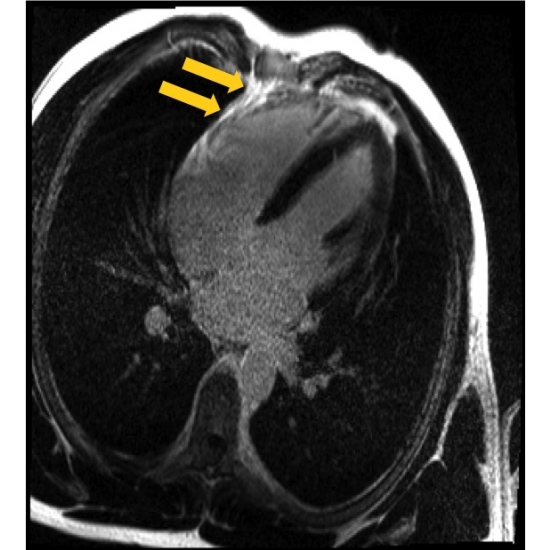

| Palpitations In A Collegiate Basketball Athlete: A Common Complaint With An Uncommon Diagnosis - Page #3 | |||